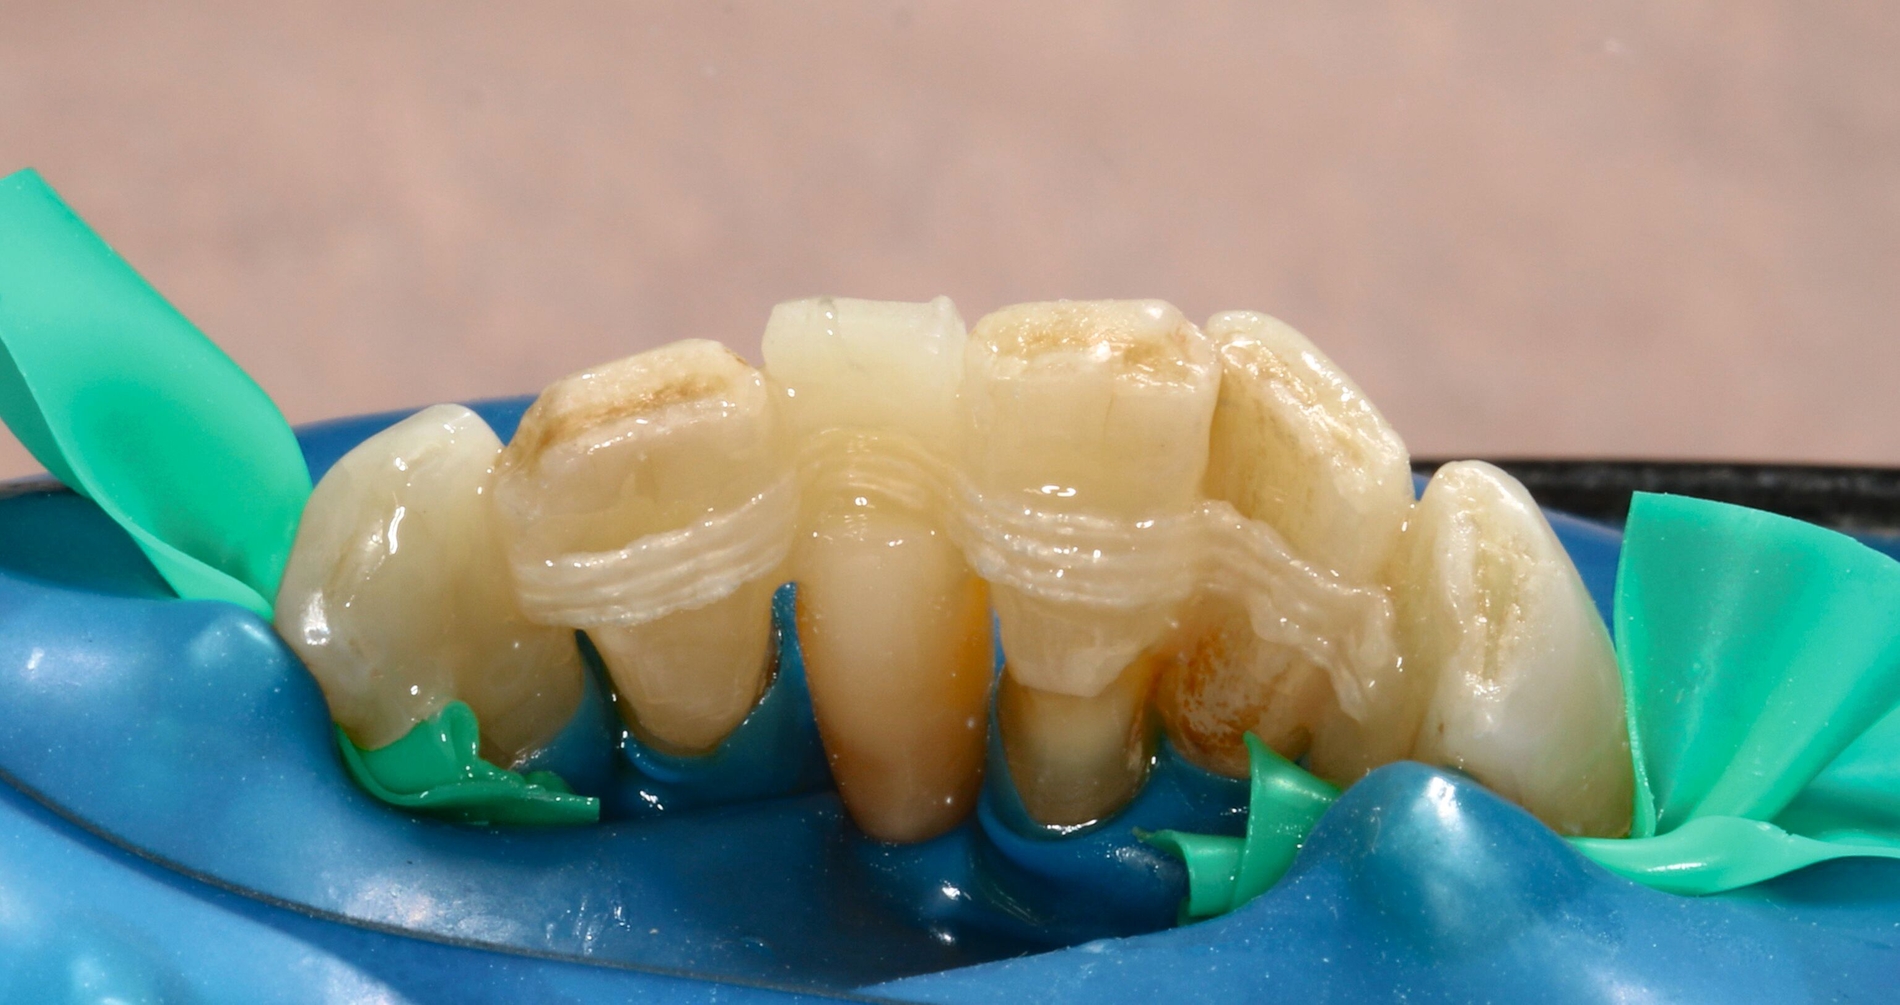

Anschließend wurde die unpräparierte Zahnoberfläche mittels 35-prozentiger Phosphorsäure (Ultra Etch, Ultradent) 60 Sekunden lang geätzt, mit einem Zwei-Komponenten-Adhäsivsystem (Optibond FL, Kerr) vorbereitet und das zur Schienung verwendete Polyethylenband (Ribbond THM Adhäsiv Verstärkungsband, Ribbond Inc.) mit Komposit (CeramX Spectra STHV & ST flow, Dentsply Sirona) fixiert. Die Polyethylenband-Oberfläche wurde großzügig mit Komposit überdeckt, ebenso wurden die Zähne mittels Komposit deutlich verblockt, um eine möglichst hohe Stabilität der Schienung zu erreichen. Gleichzeitig wurde weiterhin darauf geachtet, dass die Hygienefähigkeit der Interdentalräume erhalten bleibt (Abbildung 10).

Die Ausarbeitung erfolgte mittels Skalpellen, diamantiert-rotierenden und oszillierenden Instrumenten, rotierenden Schleifscheiben (Sof-Lex XT, 3M Espe), Gummipolierern (Diacomp Plus, EVE) sowie Finierstreifen (Sof-Lex Finierstreifen, 3M Espe) (Abbildungen 11 und 12).